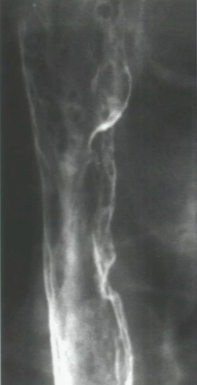

What causes this type of diverticulum?

Granulomatous disease or radiation of the chest cause a diverticulum of all layers of the wall (traction diverticulum). These will still clear food.

What is your diagnosis of this image of the esophagus?

Epiphrenic diverticulum. These are often associated with reflux and are located near the GE junction.

What could cause this?

Pseudodiverticulosis. This is a result of chronic inflammation or irritation of the submucosal glands that causes tiny outpouchings.